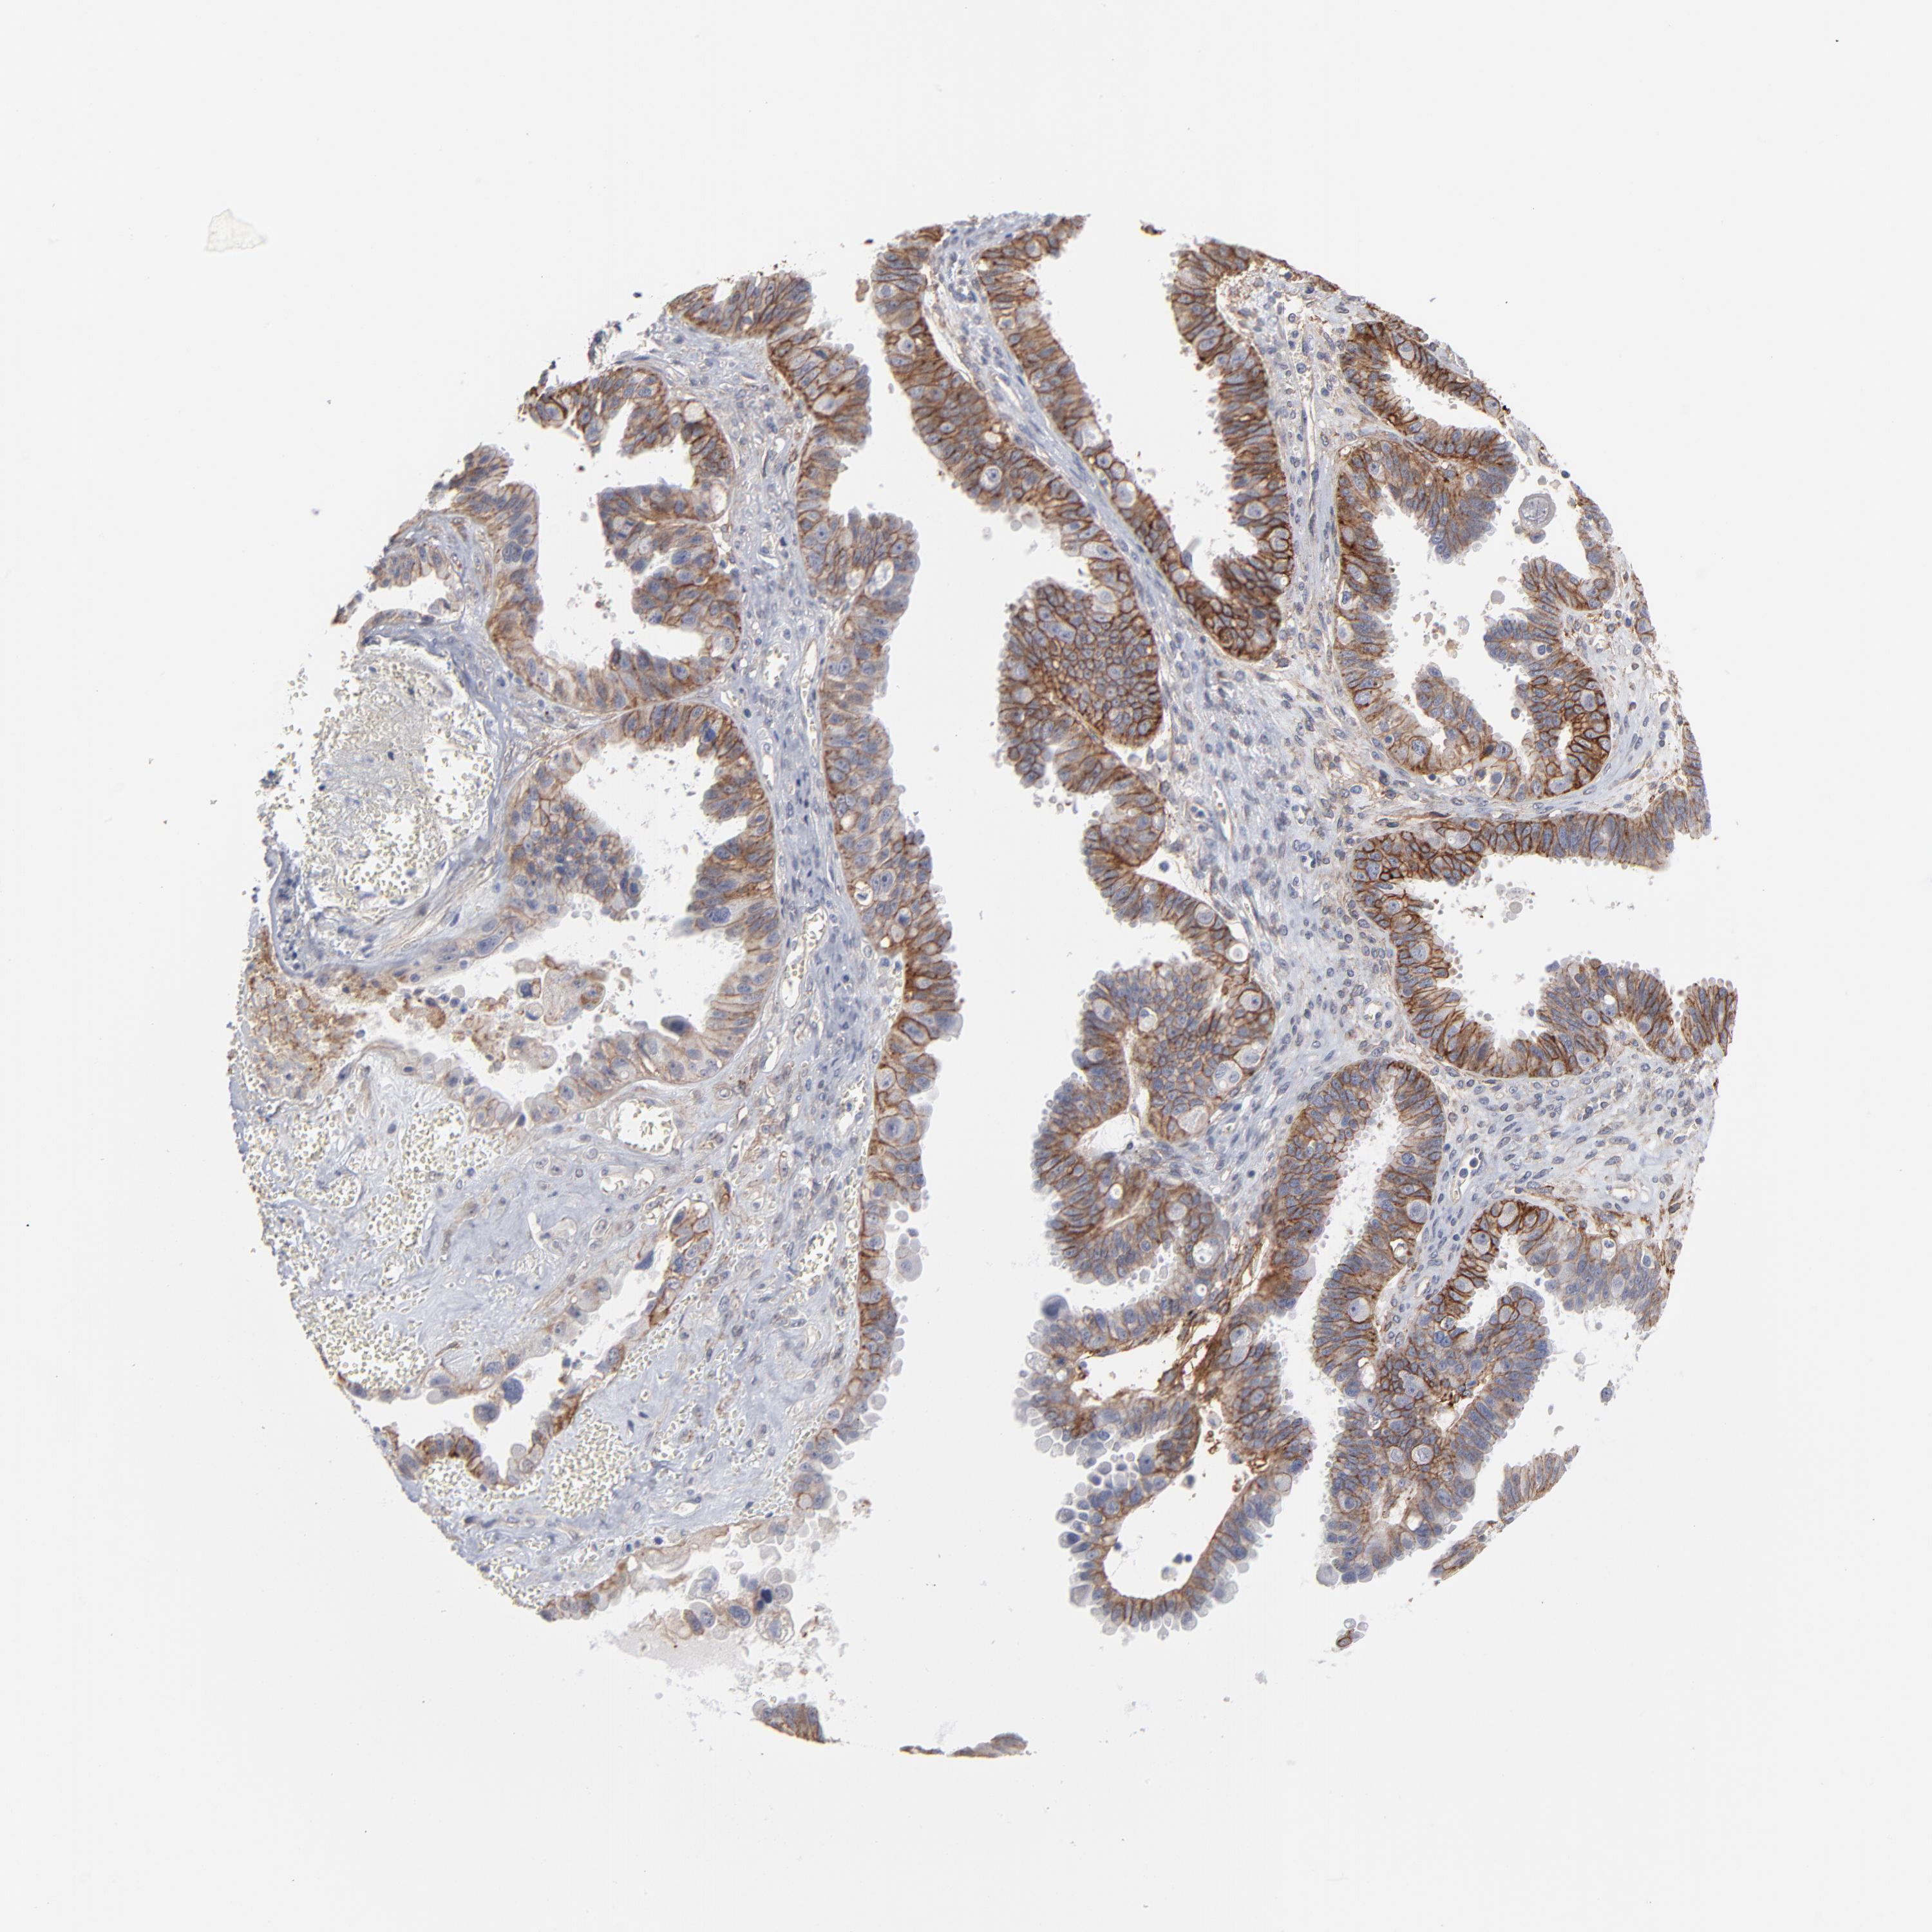

OVARIAN CANCER - Protein expressioni

A mouse-over function shows sample information and annotation data. Click on an image to view it in a full screen mode. Samples can be filtered based on level of antibody staining by selecting one or several of the following categories: high, medium, low and not detected. The assay and annotation is described here.

Note that samples used for immunohistochemistry by the Human Protein Atlas do not correspond to samples in the TCGA dataset.

Antibody stainingi

Antibody staining in the annotated cell types in the current human tissue is reported as not detected, low, medium, or high, based on conventional immunohistochemistry profiling in selected tissues. This score is based on the combination of the staining intensity and fraction of stained cells.

Each image is clickable and will lead to virtual microscopy that enables deeper exploration of all samples and also displays staining intensity scores, fraction scores and subcellular localization as well as patient and tissue information for each sample.

Antibody HPA003324

Staining

High

Medium

Low

Not detected

Intensity

Strong

Moderate

Weak

Negative

Quantity

>75%

75%-25%

<25%

None

Location

Nuclear

Cytoplasmic/membranous

Cytoplasmic/membranous,nuclear

Cystadenocarcinoma, mucinous, NOS

Carcinoma, endometroid

Cystadenocarcinoma, serous, NOS